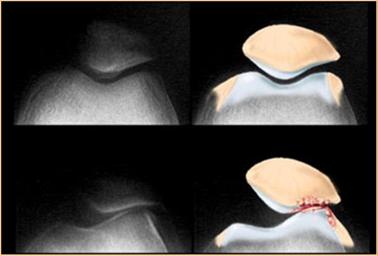

Boczne przyparcie rzepki (ELPS) to najprościej mówiąc nadmierne przesunięcie rzepki w stronę boczną, do którego dochodzi podczas ruchów kolana. Rzepka zamiast poruszać się prawidłowo po bloczku kości udowej w trakcie zgięć i wyprostów kolana przesuwa się do boku.

Poza widocznymi objawami związanymi z nieprawidłowym ruchem rzepki ELPS charakteryzuje się bólem lub sztywnością zazwyczaj w przednio – bocznej części kolana. Pacjenci skarżą się na dolegliwości bólowe związane z długim siedzeniem, a także podczas klękania, biegania, chodzenia po schodach i kucania. Bardzo ważne jest by jak najwcześniej rozpocząć indywidualnie dobrane ćwiczenia i zabiegi. Nie leczone boczne przyparcie rzepki może doprowadzić do chondromalacji, czyli uszkodzeń chrząstki stawu rzepkowo-udowego. Z czasem zwiększa się również ryzyko zwichnięcia rzepki.